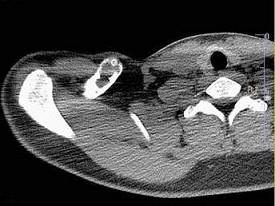

问题 男,18岁,右锁骨轻微疼痛,伴局部肿胀,结合图像,最可能的诊断是?(?)

选项 A.右锁骨正常 B.右锁骨嗜酸性肉芽肿 C.右锁骨骨囊肿 D.右锁骨骨结核 E.右锁骨骨巨细胞瘤

答案 B